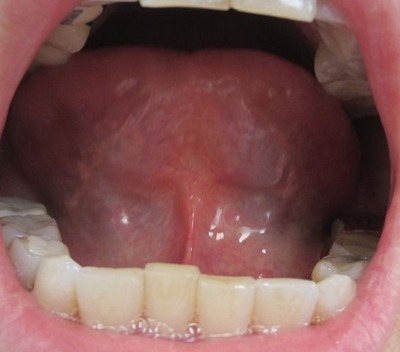

【2013年8月7日 漢方薬服用前の舌の表】

黄色の厚い苔がびっしり全体を覆っています

熱 炎症 火が非常に旺盛です

【2013年8月30日 漢方薬服用22日後の舌の表】

黄色の苔が取れて白い苔が出てきました

熱 火 炎症がかなり取れています